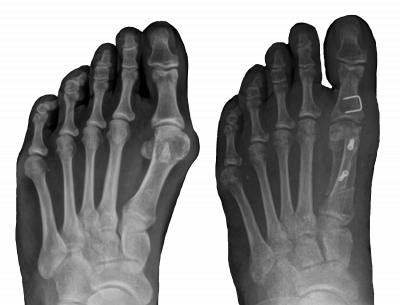

Enamuse operatsioonide eesmärgiks on pöialabaluude või varbaluude seadmine võimalikult normilähedasse asendisse. Saeme luu ettenähtud kohas läbi (tekitame luumurru) ja muudame luutükkide paiknevust. Kinnitame luutükid kaasaegsete väiksemõõduliste kruvide või klambritega õiges asendis. Kinnitusvahendid ei jää segama ning neid ei pea eemaldama. Kruvide ja klambrite kasutamine on vajalik, sest nii saame kindlustada luu kokkukasvamise parimal moel.